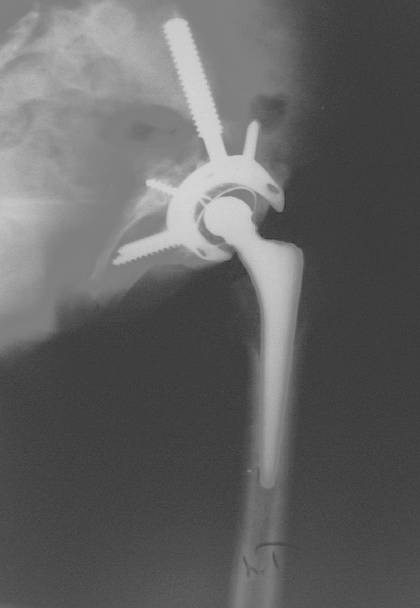

Dr. Fawzy has spent decades mastering revision surgery, including cases with severe bone loss (called "severely deficient bone stock" in medical terms). He's even designed his own special implant system for the most difficult hip revision cases - an innovation that was nominated for an award by the British Orthopaedic Association.

Dr. Fawzy designed a revolutionary revision system for severe hip bone loss - an innovation nominated for a prestigious award by the British Orthopaedic Association in 2004. This modular cage system has helped hundreds of patients with challenging cases.